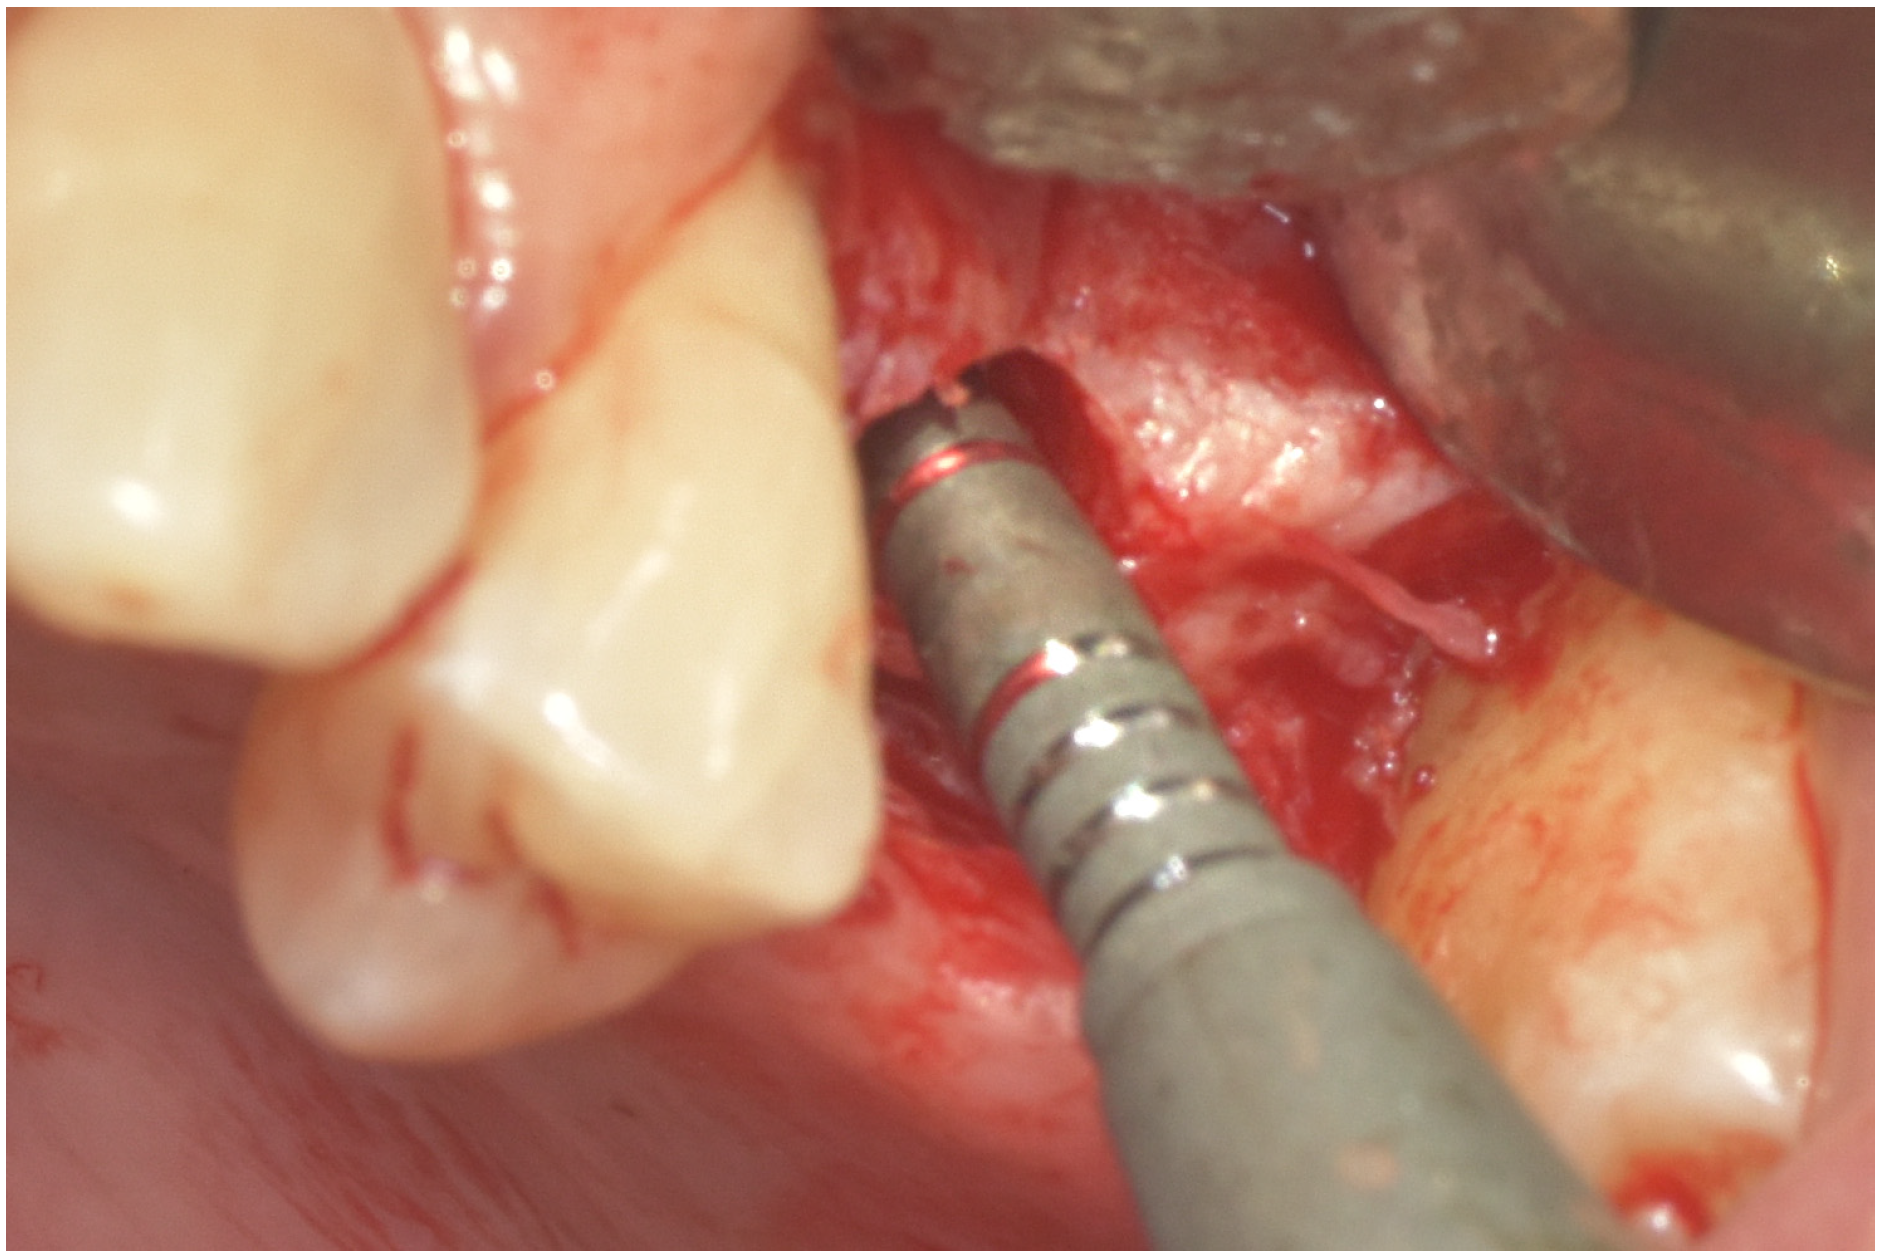

Transcrestal Sinus Elevation with Implant Placement Using Autogenous Bone Supporting Multilayer Crosslinked Collagen Xenograft Scaffolding: A Case Series

2. Materials and Methods